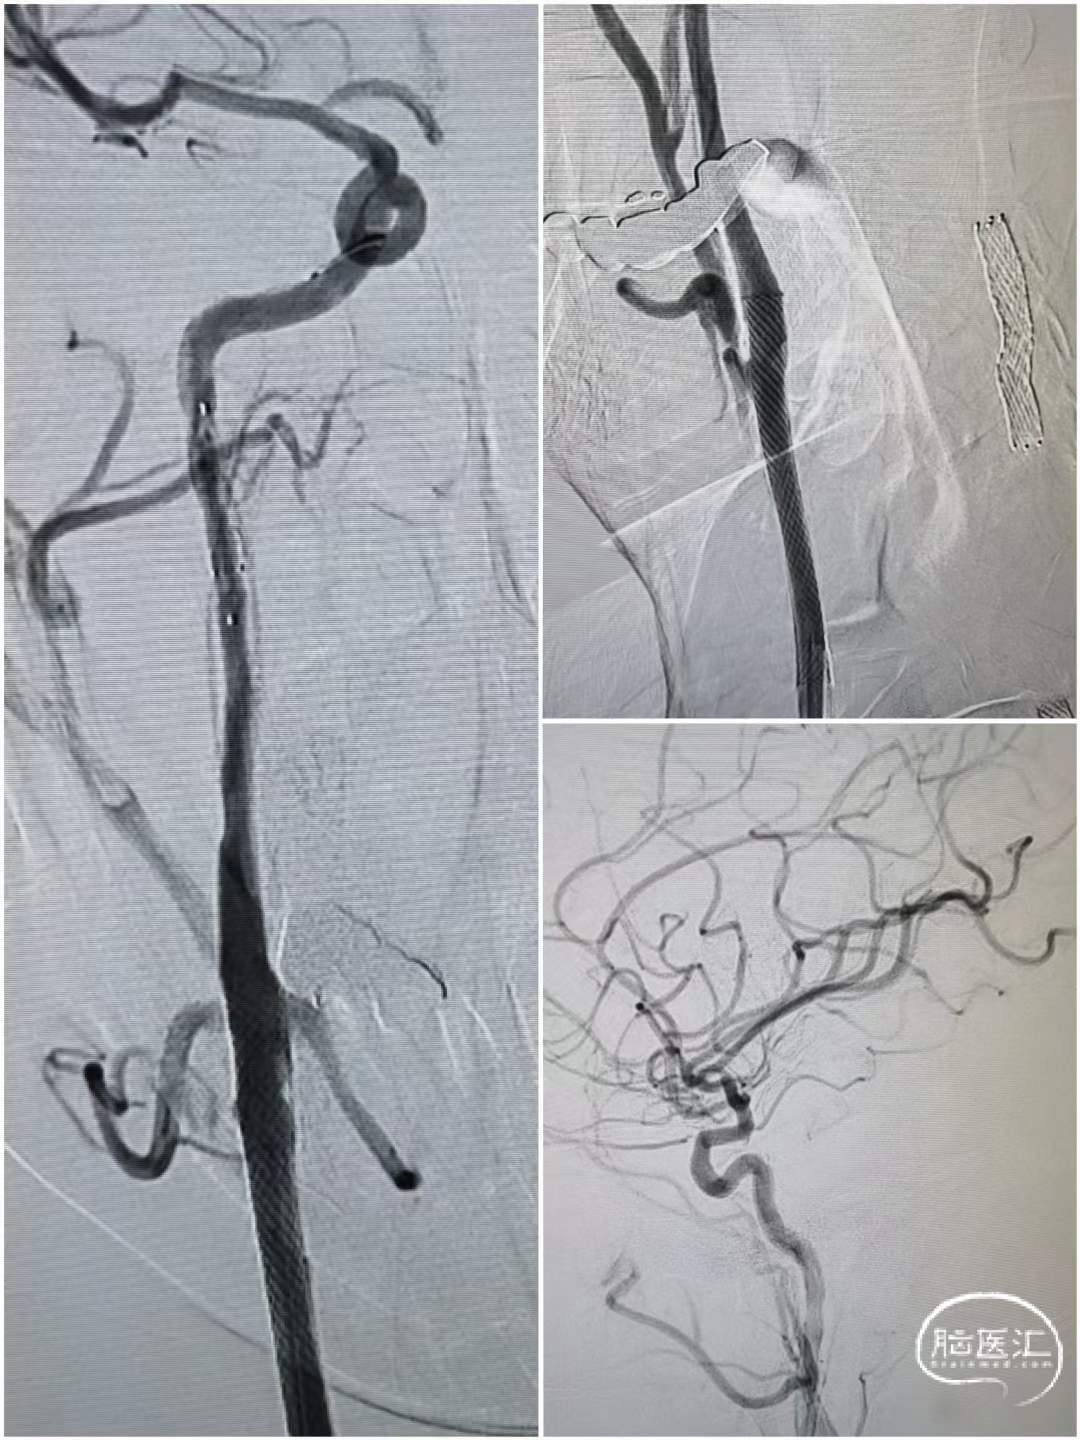

术后造影

造影可见:双侧病变改善,患者症状好转安返病房。